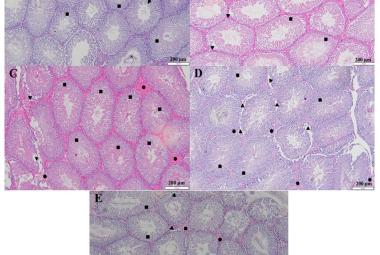

Parkinson’s disease (PD) is a neurological condition affecting the motor functions of the brain, characterised by the degeneration of dopaminergic neurons in the substantia nigra pars compacta region. The primary symptoms include dyskinesia, bradykinesia and resting tremors. This study investigated the potential impacts of Mitragyna speciosa or known as kratom on zebrafish with PD. 1-methyl-1,2,3,6-tetrahydropyridine (MPTP) solution was administered intraperitoneally to zebrafish to develop Parkinson’s symptoms in 2 to 3 days, followed by three concentrations treatment of kratom, for 28 days. On day 28, locomotor behaviour was evaluated to determine the duration spent in the top, middle, and bottom zones, total distance travelled and swimming speed. Then, the zebrafish were euthanised and preserved in a 10% formalin solution. Fixed zebrafish were processed and embedded in paraffin blocks for haematoxylin and eosin, and cresyl violet staining. The results of treatment groups showed that kratom had a neuroprotective impact, increasing time spent from bottom to top zone, distance travelled and swimming speed compared to the negative group. Moreover, the treatment groups experienced a rise in neuron regeneration and an enhancement in neuron appearance following a 28-day exposure to kratom. In conclusion, kratom shows promise as a potential treatment for PD by effectively reducing symptoms and improving movement.